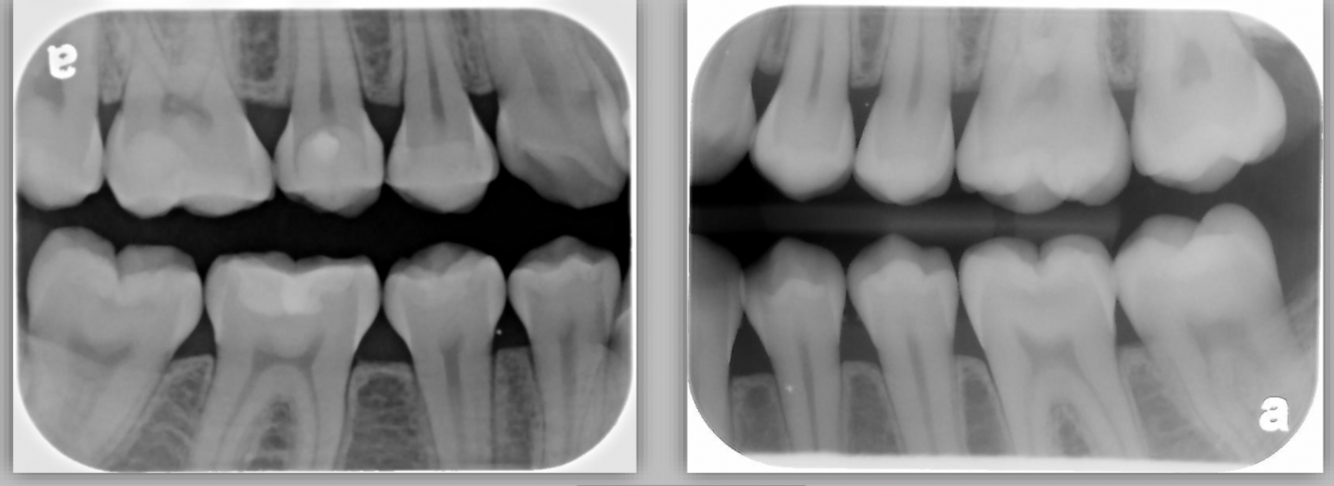

What type of radiograph is seen in the following images?

A

horizontal bitwings

Does the following image show correct or incorrect angulation for a bitewing?

correct

Q

incorrect